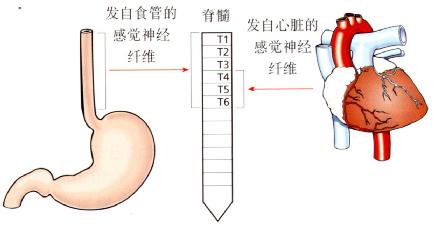

非心源性胸痛(NCCP)是指临床表现为典型心脏病样胸痛,但检查并未发现心脏疾病。疼痛可能源于食管(图3.13)。

食管的感觉神经纤维随交感神经于T1至T6之间进入脊髓(主要是T4到T6),此区域亦接收心脏的感觉神经输入。

这种感觉神经的会聚可解释为何源于食管的痛感可与心脏的疼痛相混淆,常称之为牵涉痛。

图3.13食管和心脏的感觉神经输入。